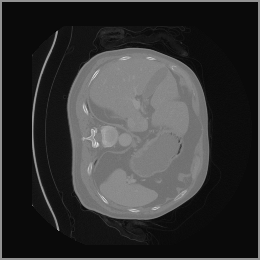

The motivation for this work arises from the need to address these limitations in the synthesis of 3D medical images. Current techniques do not produce high-resolution 3D images that preserve spatial coherence and capture the full complexity of medical data, as shown in Figure 2, 5. The development of advanced 3D generative models tailored specifically for medical imaging could not only improve the quality of synthetic medical images but also help alleviate data scarcity, enhance privacy protection, reduce computational requirement and ultimately advance the use of deep learning in healthcare applications.

To demonstrate the advantages of 3D semantic image synthesis over 2D semantic semantic image synthesis, we conducted a detailed comparison with the SegGuidedDiff [26] model. SegGuidedDiff generates medical images based on 2D semantic maps, producing individual 2D slices that are later stacked to form a 3D image. However, this approach has limitations in capturing spatial continuity and coherence across slices, which is critical for representing the spatial structure of 3D medical images. As a result, inconsistencies often arise between different slices, particularly in preserving anatomical structures across the coronal and sagittal planes. The generated images exhibit varying levels of denoising, resulting in differences in brightness and sharpness across the images. This inconsistency in denoising can lead to noticeable variations in visual quality, where some regions appear clearer and others less distinct.

As shown in Figure 5, the generated slices exhibit high consistency across adjacent slices. The anatomical structures and semantic patterns are smoothly and coherently preserved between slices, indicating that our model is capable of generating 3D-consistent synthetic images rather than isolated 2D slices.

Figure 8 further supports these findings: the images generated by Med-LSDM preserve spatial coherence across coronal and sagittal planes, whereas those from SegGuidedDiff show noticeable inconsistencies. These artifacts likely result from the 2D nature of SegGuidedDiff, which fails to account for 3D spatial relationships. In contrast, our model’s volumetric diffusion framework inherently preserves anatomical consistency, highlighting its advanta in synthesizing high-fidelity 3D medical images.